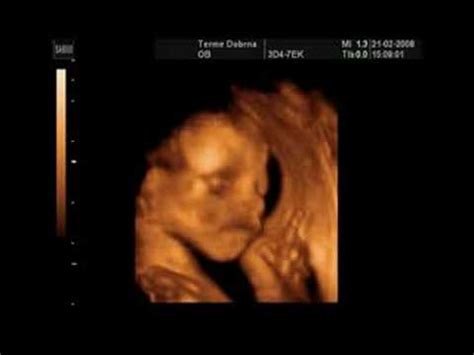

- Odsotnost ploda: Na ultrazvoku ni mogoče zaznati zarodka ali njegovih srčnih utripov.